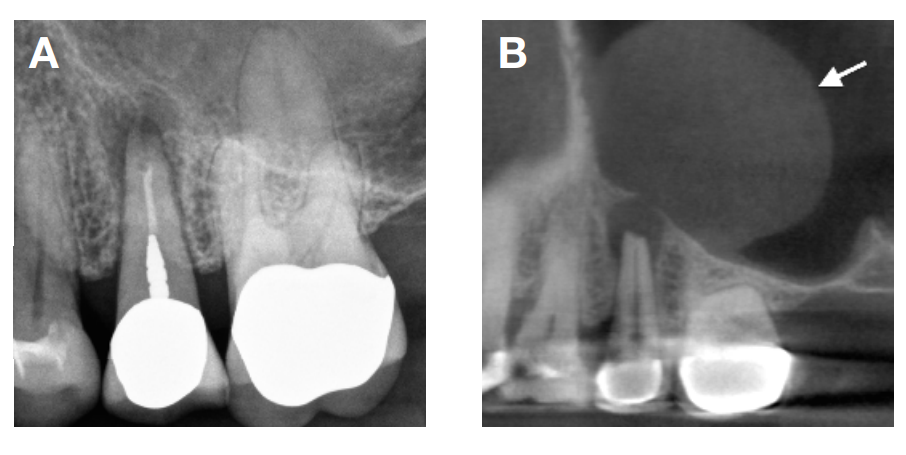

“需要强调一点,”他补充到:“这次诊疗多亏了数字化技术,CBCT影像更好地辅助了诊断。”一般牙科X光片角度单一。上颚后牙外侧的很多解剖构造会阻挡在前面,遮盖或隐藏牙齿根尖周围发炎的变化;成像技术的限制不太容易让医生发现牙根尖周围的状况。

研究和临床实践也发现,牙齿感染造成鼻窦膜的变化,需要被放射学仪器侦测到的情况下才更容易被发现。因此,使用CBCT做检测可达到77 %的发现比率,而一般X光片仅为 19 %。所以在诊疗上,CBCT 能提供更为准确的口腔讯息。